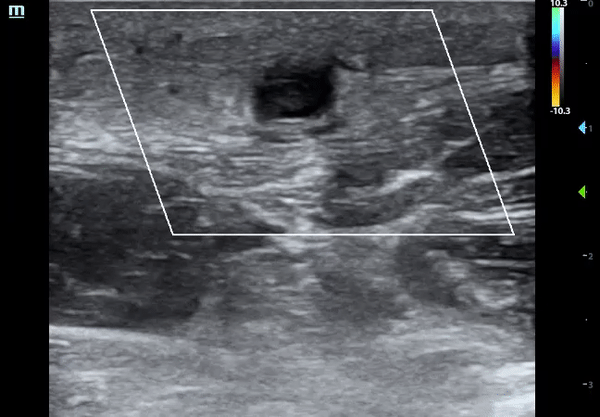

Llnear probe in short axis over the mid forearm revealed a superficial, well-circumscribed, hypoechoic structure with intraluminal echogenicity that was not compressible.

Color flow applied and no flow within the structure was noted